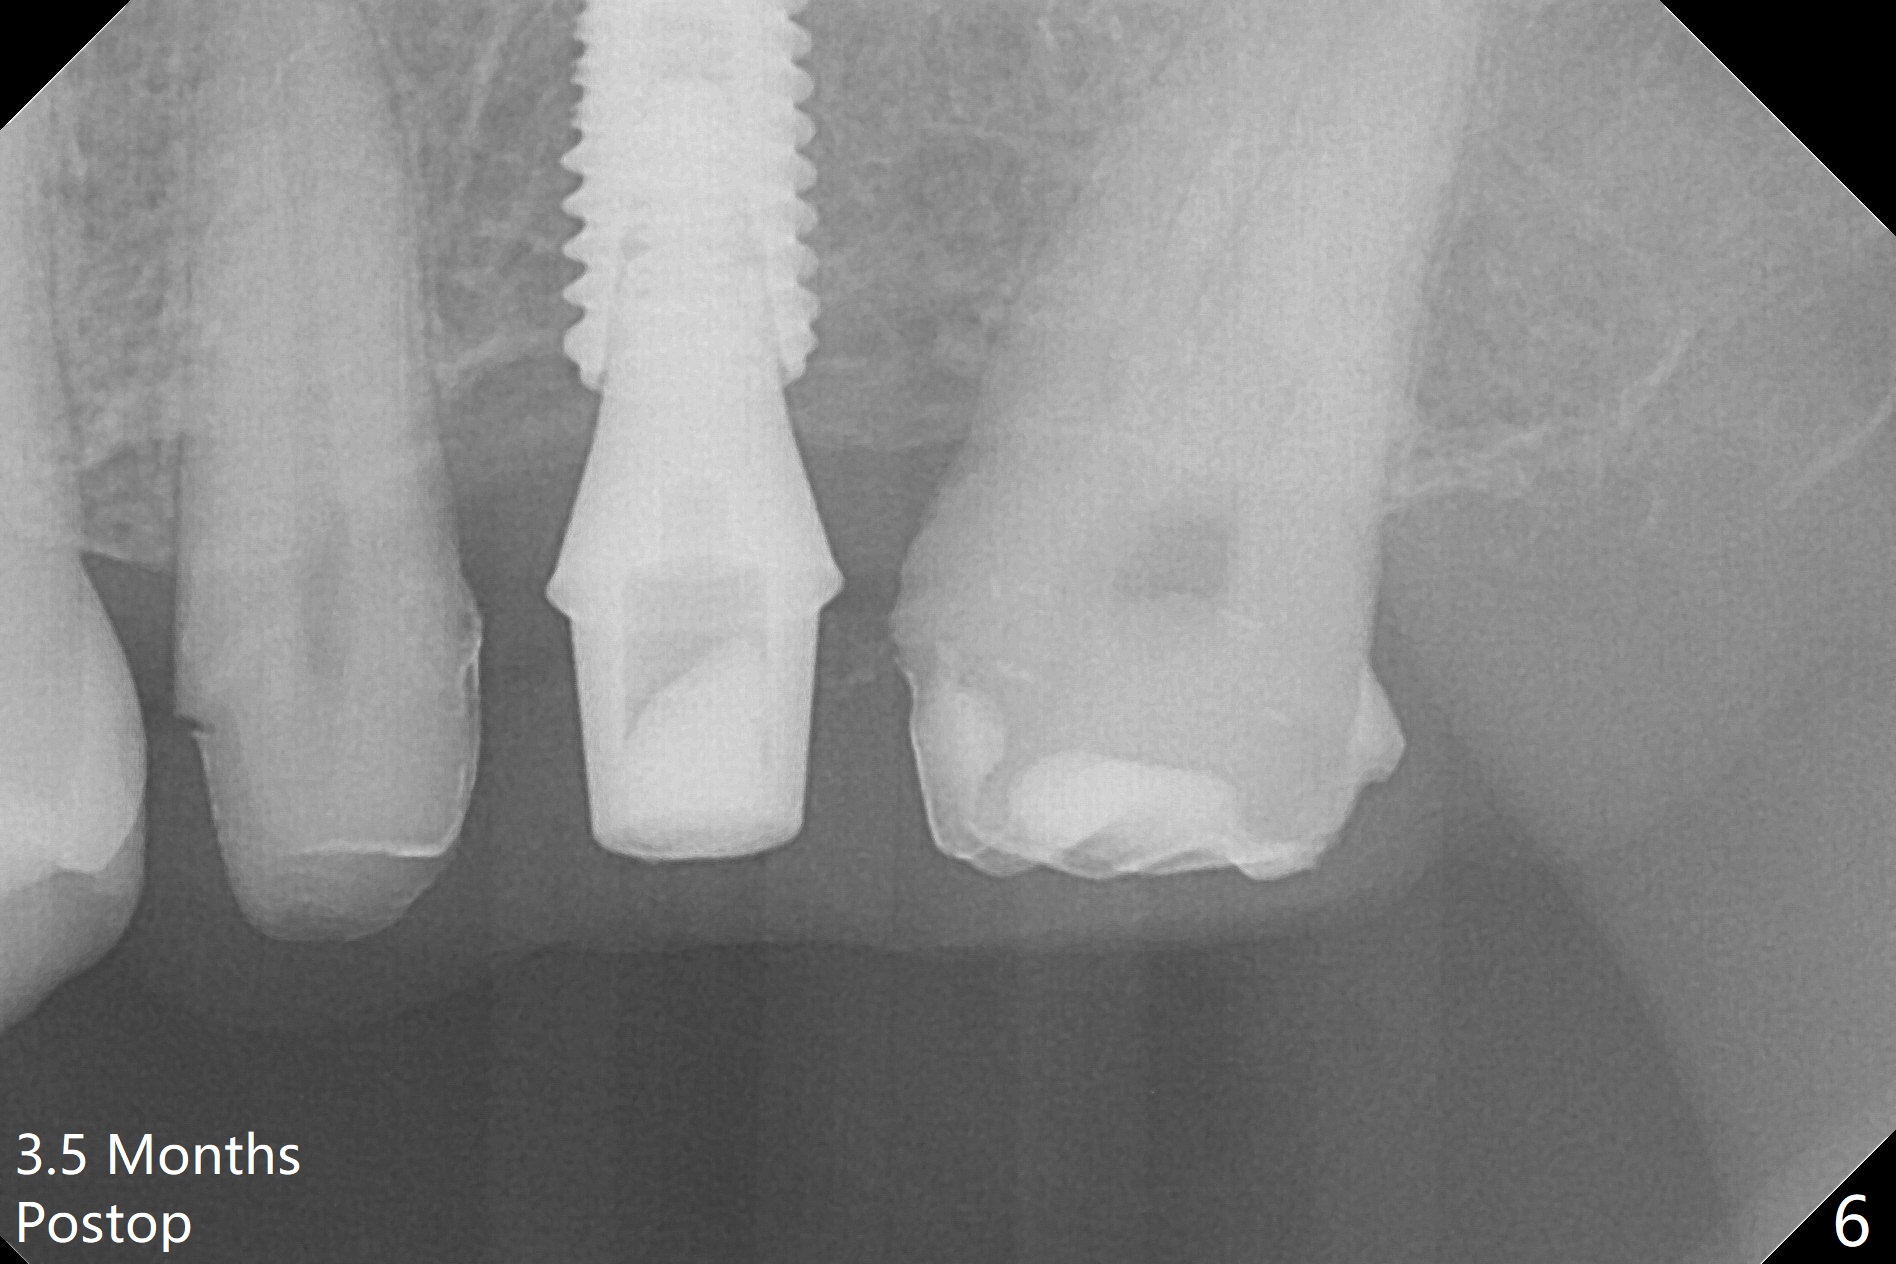

#13-15 FPD has not been used properly because of discomfort for 2 years. Before its removal, the discomfort derives from probing of the distal of #13 and mesial of #15, corresponding to calculus in the proximal areas. SRP is performed in UL quadrant after FPD removal. Bone density at the crest of the edentulous area is normal, while that of the medulla is low. After determination of trajectory and depth of initial osteotomy (Fig.1 (5 mm straight incision)), the site is underprep for a 4.5x13 mm Implant. Following adjustment, the implant is placed slightly subcrestal (Fig.2,3). It is possible that the discomfort of the previous FPD is due to overload, as suggested by the prominent buccal plate at #13 and 15, as compared to that of #12 (Fig.4 (5.2x4.5(3) mm cementation abutment at #14). Postop follow up shows that the tooth #15 may need RCT. The implant seems to enter the sinus (Fig.5 (2.5 months postop)) and be ready for restoration 3.5 months postop (Fig.6).